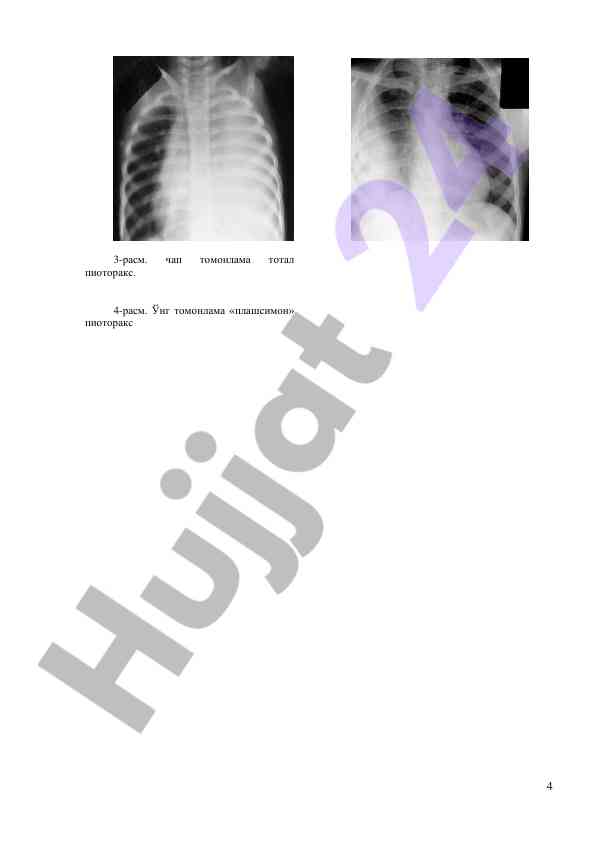

Ushbu ish bolalarda upka va plevraning yiringli kasalliklarini, ularning sabablari va patogenezi haqida muhim ma'lumotlarni taqdim etadi. Bemor hayoti uchun xavfli holatlar va kasallikning og'irligi haqida tavsiyalarni o'z ichiga oladi.